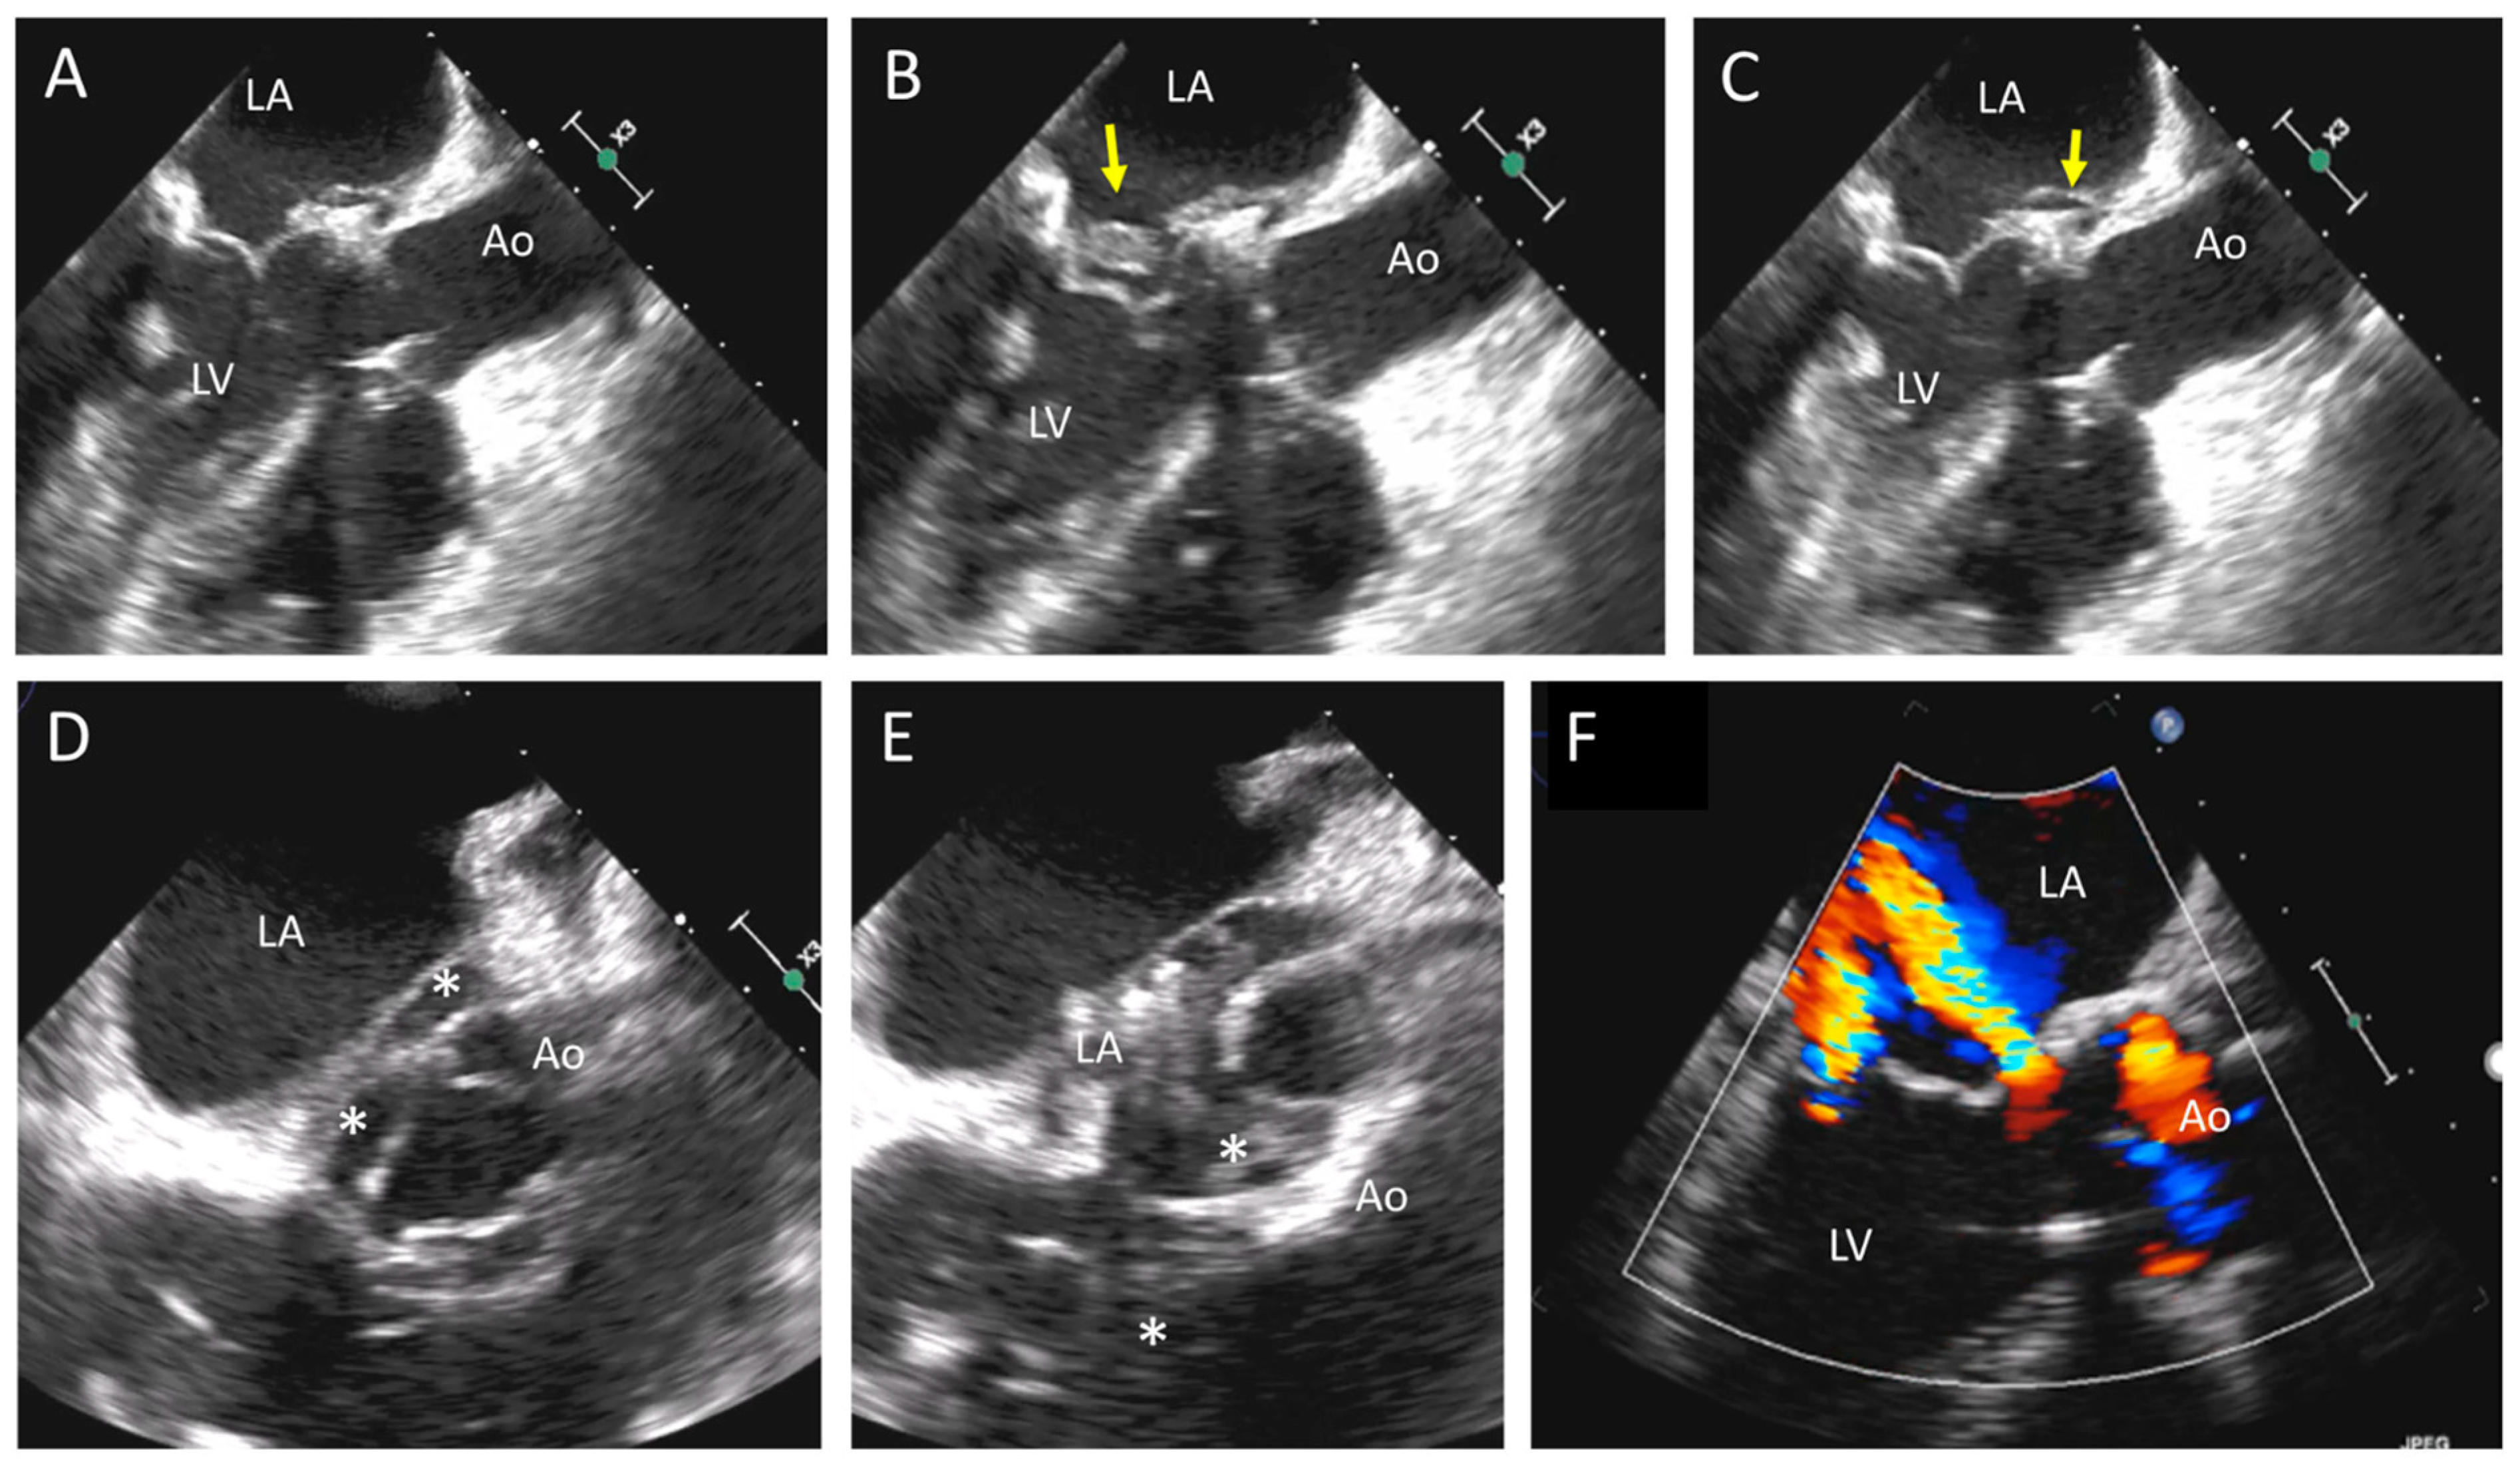

| TTE, TEE | Leaflet and/or ring thickening with diffuse or focal hyperechogenicity (calcifications). Reduced leaflet mobility. Leaflets’ fenestration, avulsion, or perforation. Stenosis or regurgitation. | Iso-hypoechogenic mass adherent to leaflets and ring, with leaflet thickening. Normal or reduced cusp mobility. More often, stenosis; regurgitation is uncommon. | Vegetations, diffuse or focal leaflets thickening, cusps perforation, wear or tear or cusp avulsion. Vegetation motion independent to cusps motion. Paravalvular complications: abscess, pseudo-aneurysm, fistula or dehiscence (and in some cases valve rocking) |

| CCT | Pannus (hypodense): HU ≥ 145; semicircular or circular structure located along leaflets’ surface or stent. Hyperdense leaflet thickening with or without calcifications, along with or without reduced mobility. | No calcifications. HU < 145. Hypoattenuated leaflet thickening (HALT), affecting (HAM) or reducing (RLM) leaflet motion. In some cases, large hypoattenuated mass. | Hypoattenuated mass adherent to leaflets or stent. Paravalvular complications: abscess, pseudo-aneurysm, fistula, or dehiscence. |